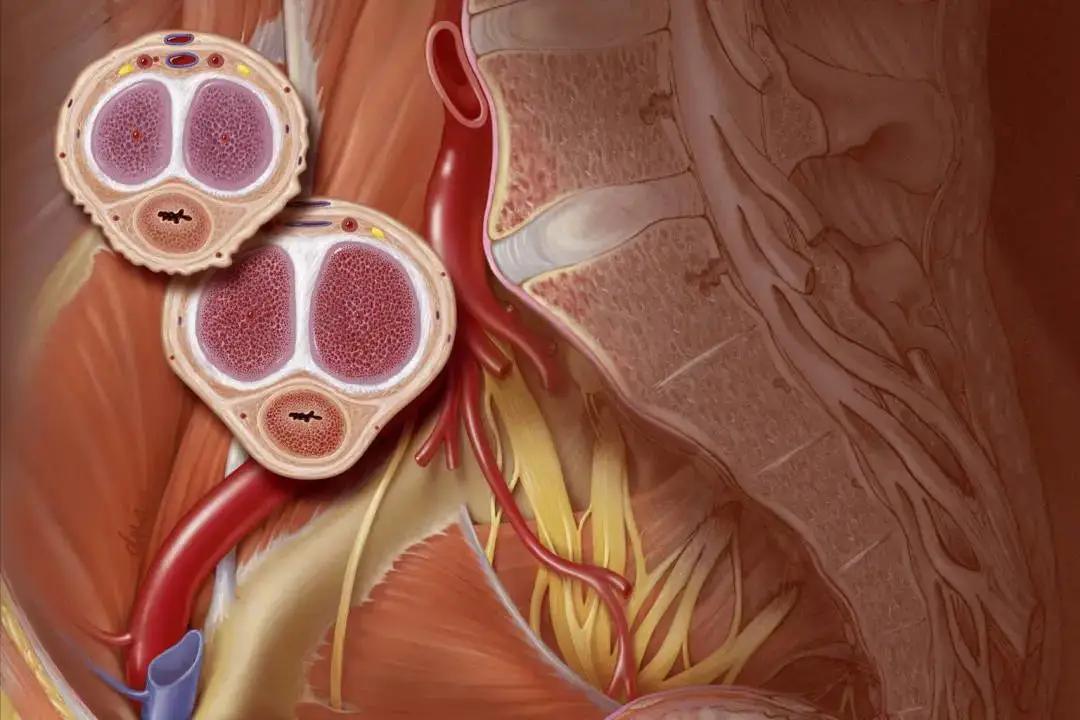

所以,第一个信号是走路腿疼,尤其是那种走一段疼、休息下又能缓解的,别老想着是缺钙或者劳损,最可疑的是周围动脉硬化闭塞。

这类病人去医院,首选血管外科或心血管外科,检查可以做下肢动脉彩超、踝肱指数(ABI)或CTA。

腿部问题,查下肢动脉彩超、CTA;